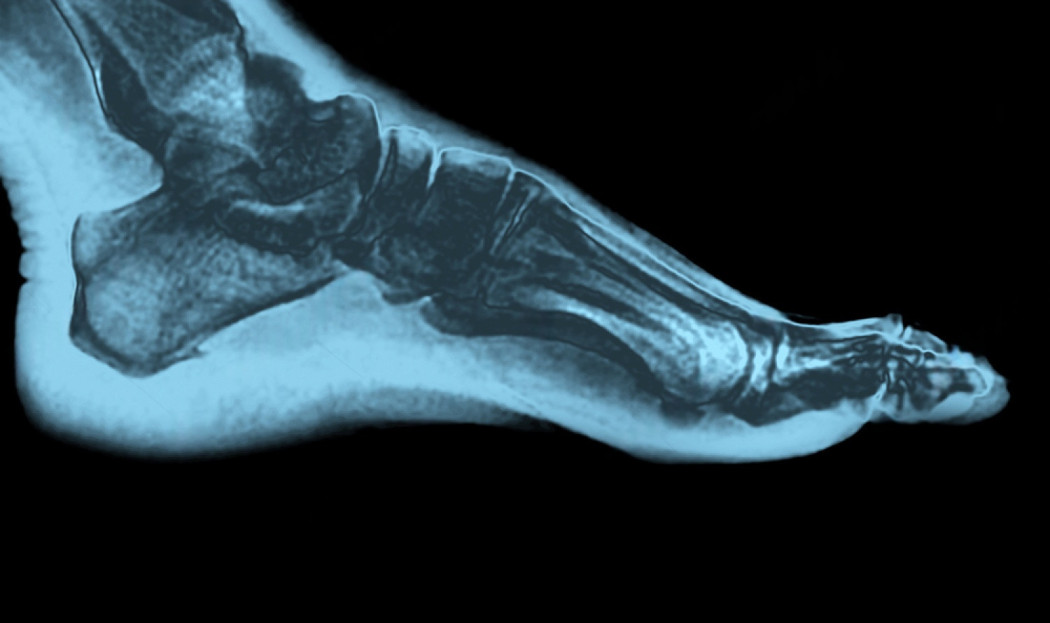

• Clinical exam: Gait, hindfoot alignment, forefoot abduction, calf flexibility, ligament laxity (anterior drawer/talar tilt), and tenderness mapping.

• Weight‑bearing X‑rays: AP/lateral/oblique, hindfoot alignment view; hallux angles; Meary’s angle; talar uncoverage.

• MRI: PTT tears, spring ligament integrity, peroneals, osteochondral lesions of talus, and occult impingement.

We line up your symptoms with imaging so treatment targets the true pain generator.